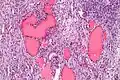

-

Higher magnification